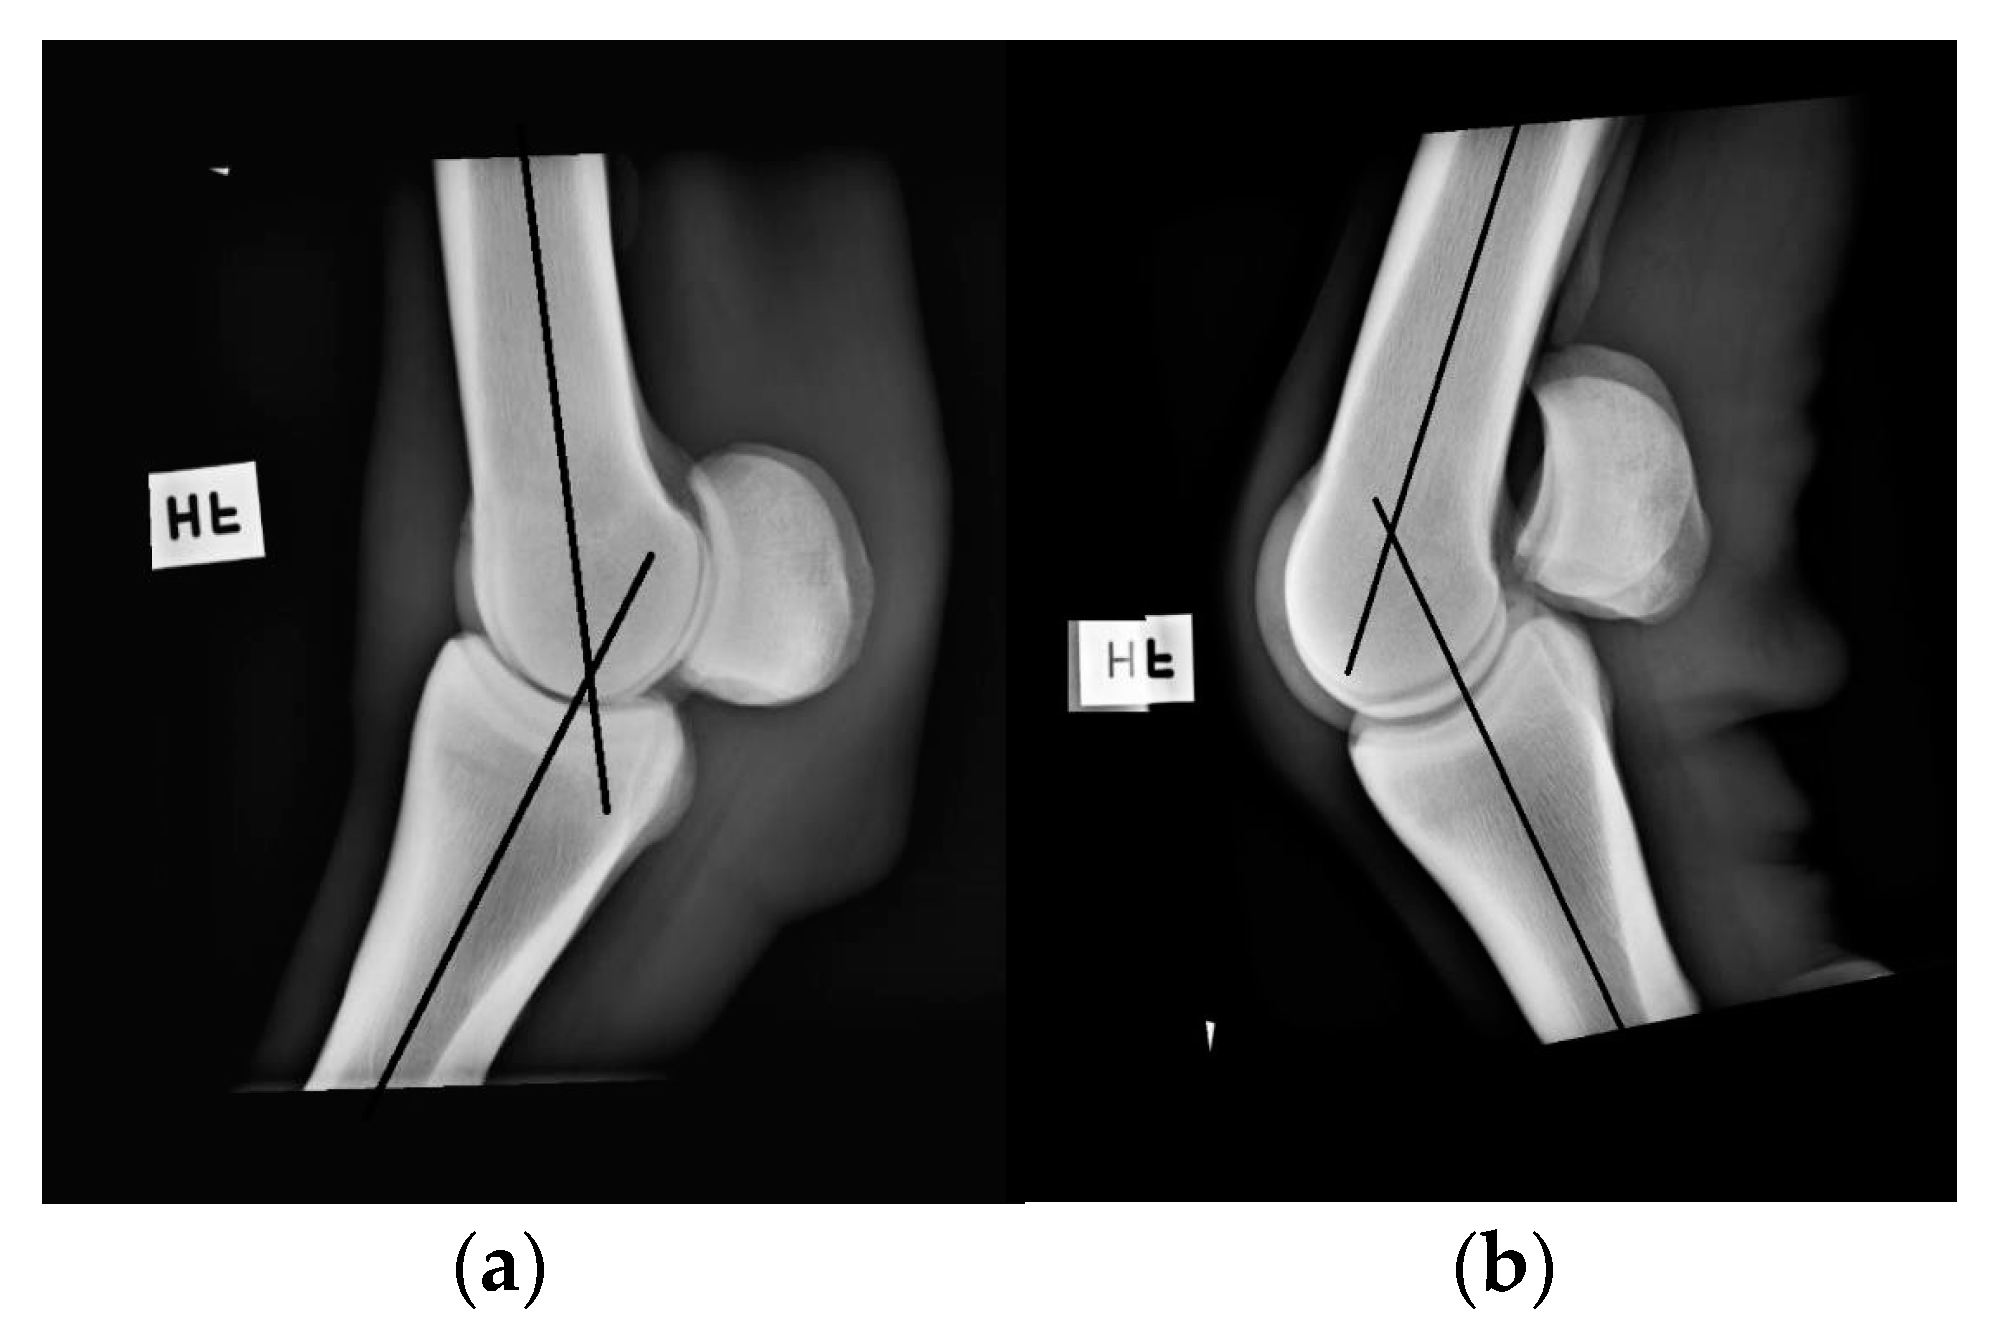

2.5. Radiography